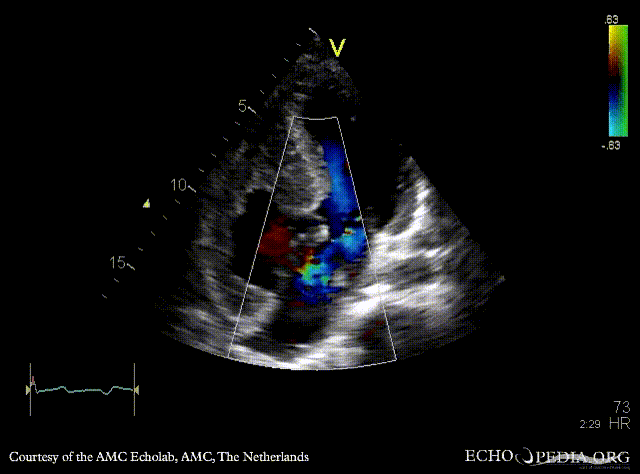

A4CH: Color Doppler signal of AVSD